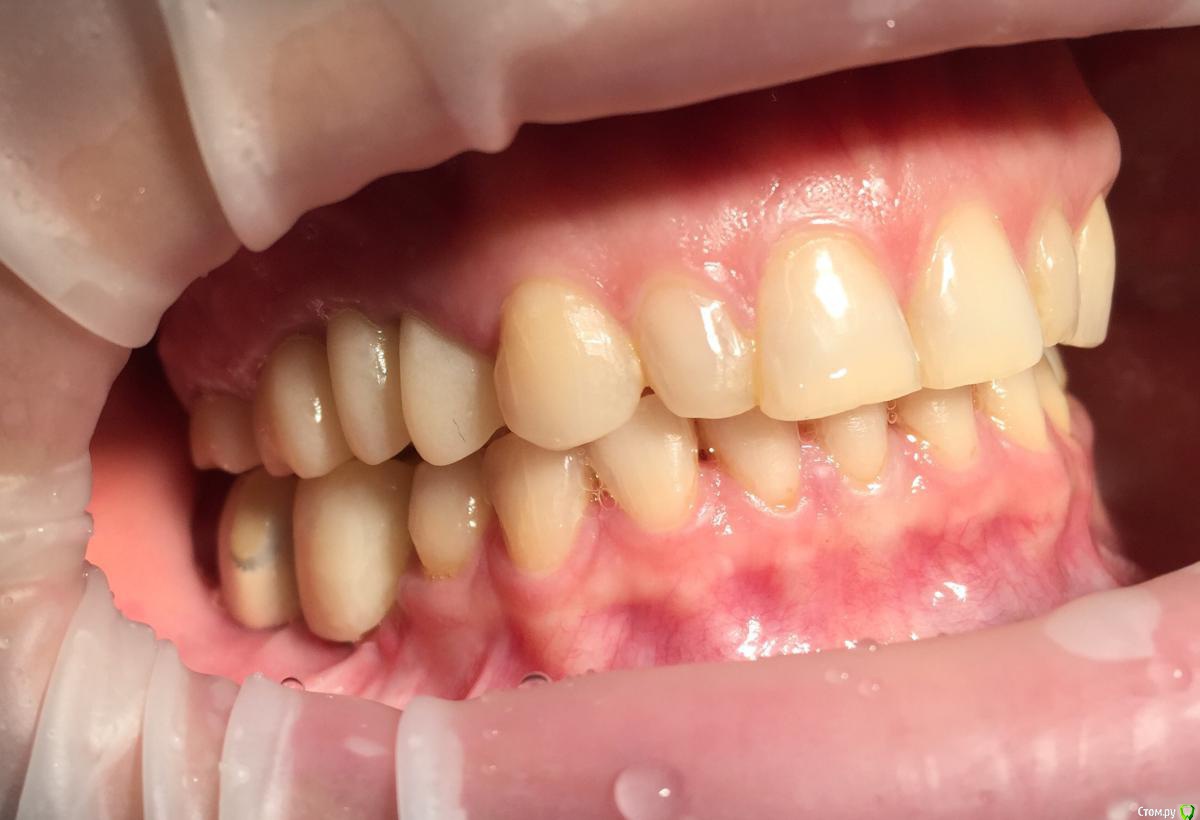

Глеб Митрофанов Опубликовано 12 сентября, 2015 Поделиться Опубликовано 12 сентября, 2015 (изменено) Направлена ортопедом , к которому пришла от другого хирурга и ортопеда , которые оперировали и изготавливали времянки соответственно . Пришла с просьбой - хочу сосочки ! Изменено 12 сентября, 2015 пользователем Глеб Митрофанов Ссылка на комментарий

Глеб Митрофанов Опубликовано 12 сентября, 2015 Автор Поделиться Опубликовано 12 сентября, 2015 А какой вопрос? С какой целью написали?Что возможно сделать , чтоб сделать максимально приближенное к желаемому ? Работа с мягкими тканями , времянками ?? Ссылка на комментарий

faity Опубликовано 12 сентября, 2015 Поделиться Опубликовано 12 сентября, 2015 пластика с бугров наверху, снизу полностью переделывать ортопедию и делать пластику с бугров. Гамборена вчера показывал как))) carlos показывает уже год 4 Ссылка на комментарий

Aquarius Опубликовано 12 сентября, 2015 Поделиться Опубликовано 12 сентября, 2015 Что возможно сделать , чтоб сделать максимально приближенное к желаемому ? Работа с мягкими тканями , времянками ??Если имплант не глушить, то по моему никак Ссылка на комментарий

Глеб Митрофанов Опубликовано 12 сентября, 2015 Автор Поделиться Опубликовано 12 сентября, 2015 Если имплант не глушить, то....Первая мысль , которая пришла в голову , заглушить винты Ссылка на комментарий

Mane Опубликовано 12 сентября, 2015 Поделиться Опубликовано 12 сентября, 2015 снимаешь временную коронкупересаживаешь сст с бугра на тонкий формировательждешь месяцоцениваешьпротезируешь 2 Ссылка на комментарий